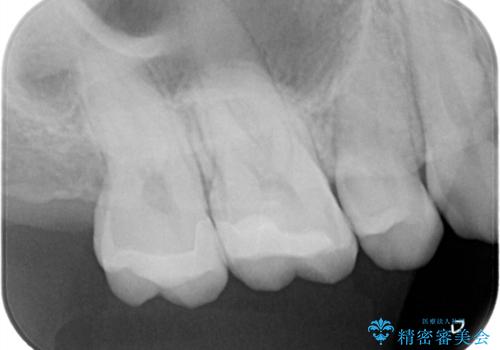

- 金属を外してセラミックを入れたいことを主訴に来院された患者さんです。

セラミックインレーにて修復を行いました。